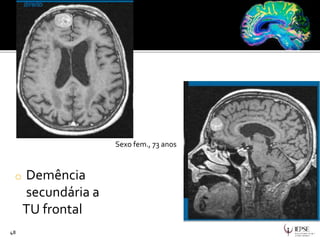

o Demência

secundária a

TU frontal

48

Sexo fem., 73 anos